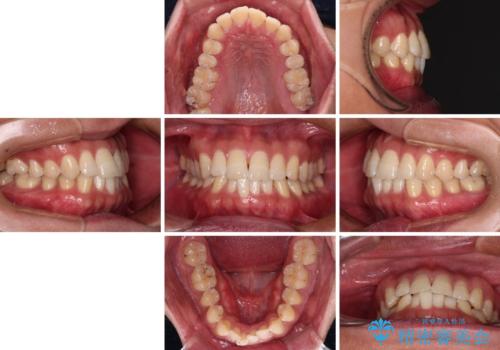

- 前歯のデコボコを気にして来院された患者様です。

インビザラインによるマウスピース矯正も適用となる歯列でしたが、できる限り自己管理の煩わしさのない状態で治したいとのことで、ワイヤー装置にて矯正治療を行うこととしました。

予定していた期間より長くかかりましたが、1年強できれいな歯列に仕上がりました。